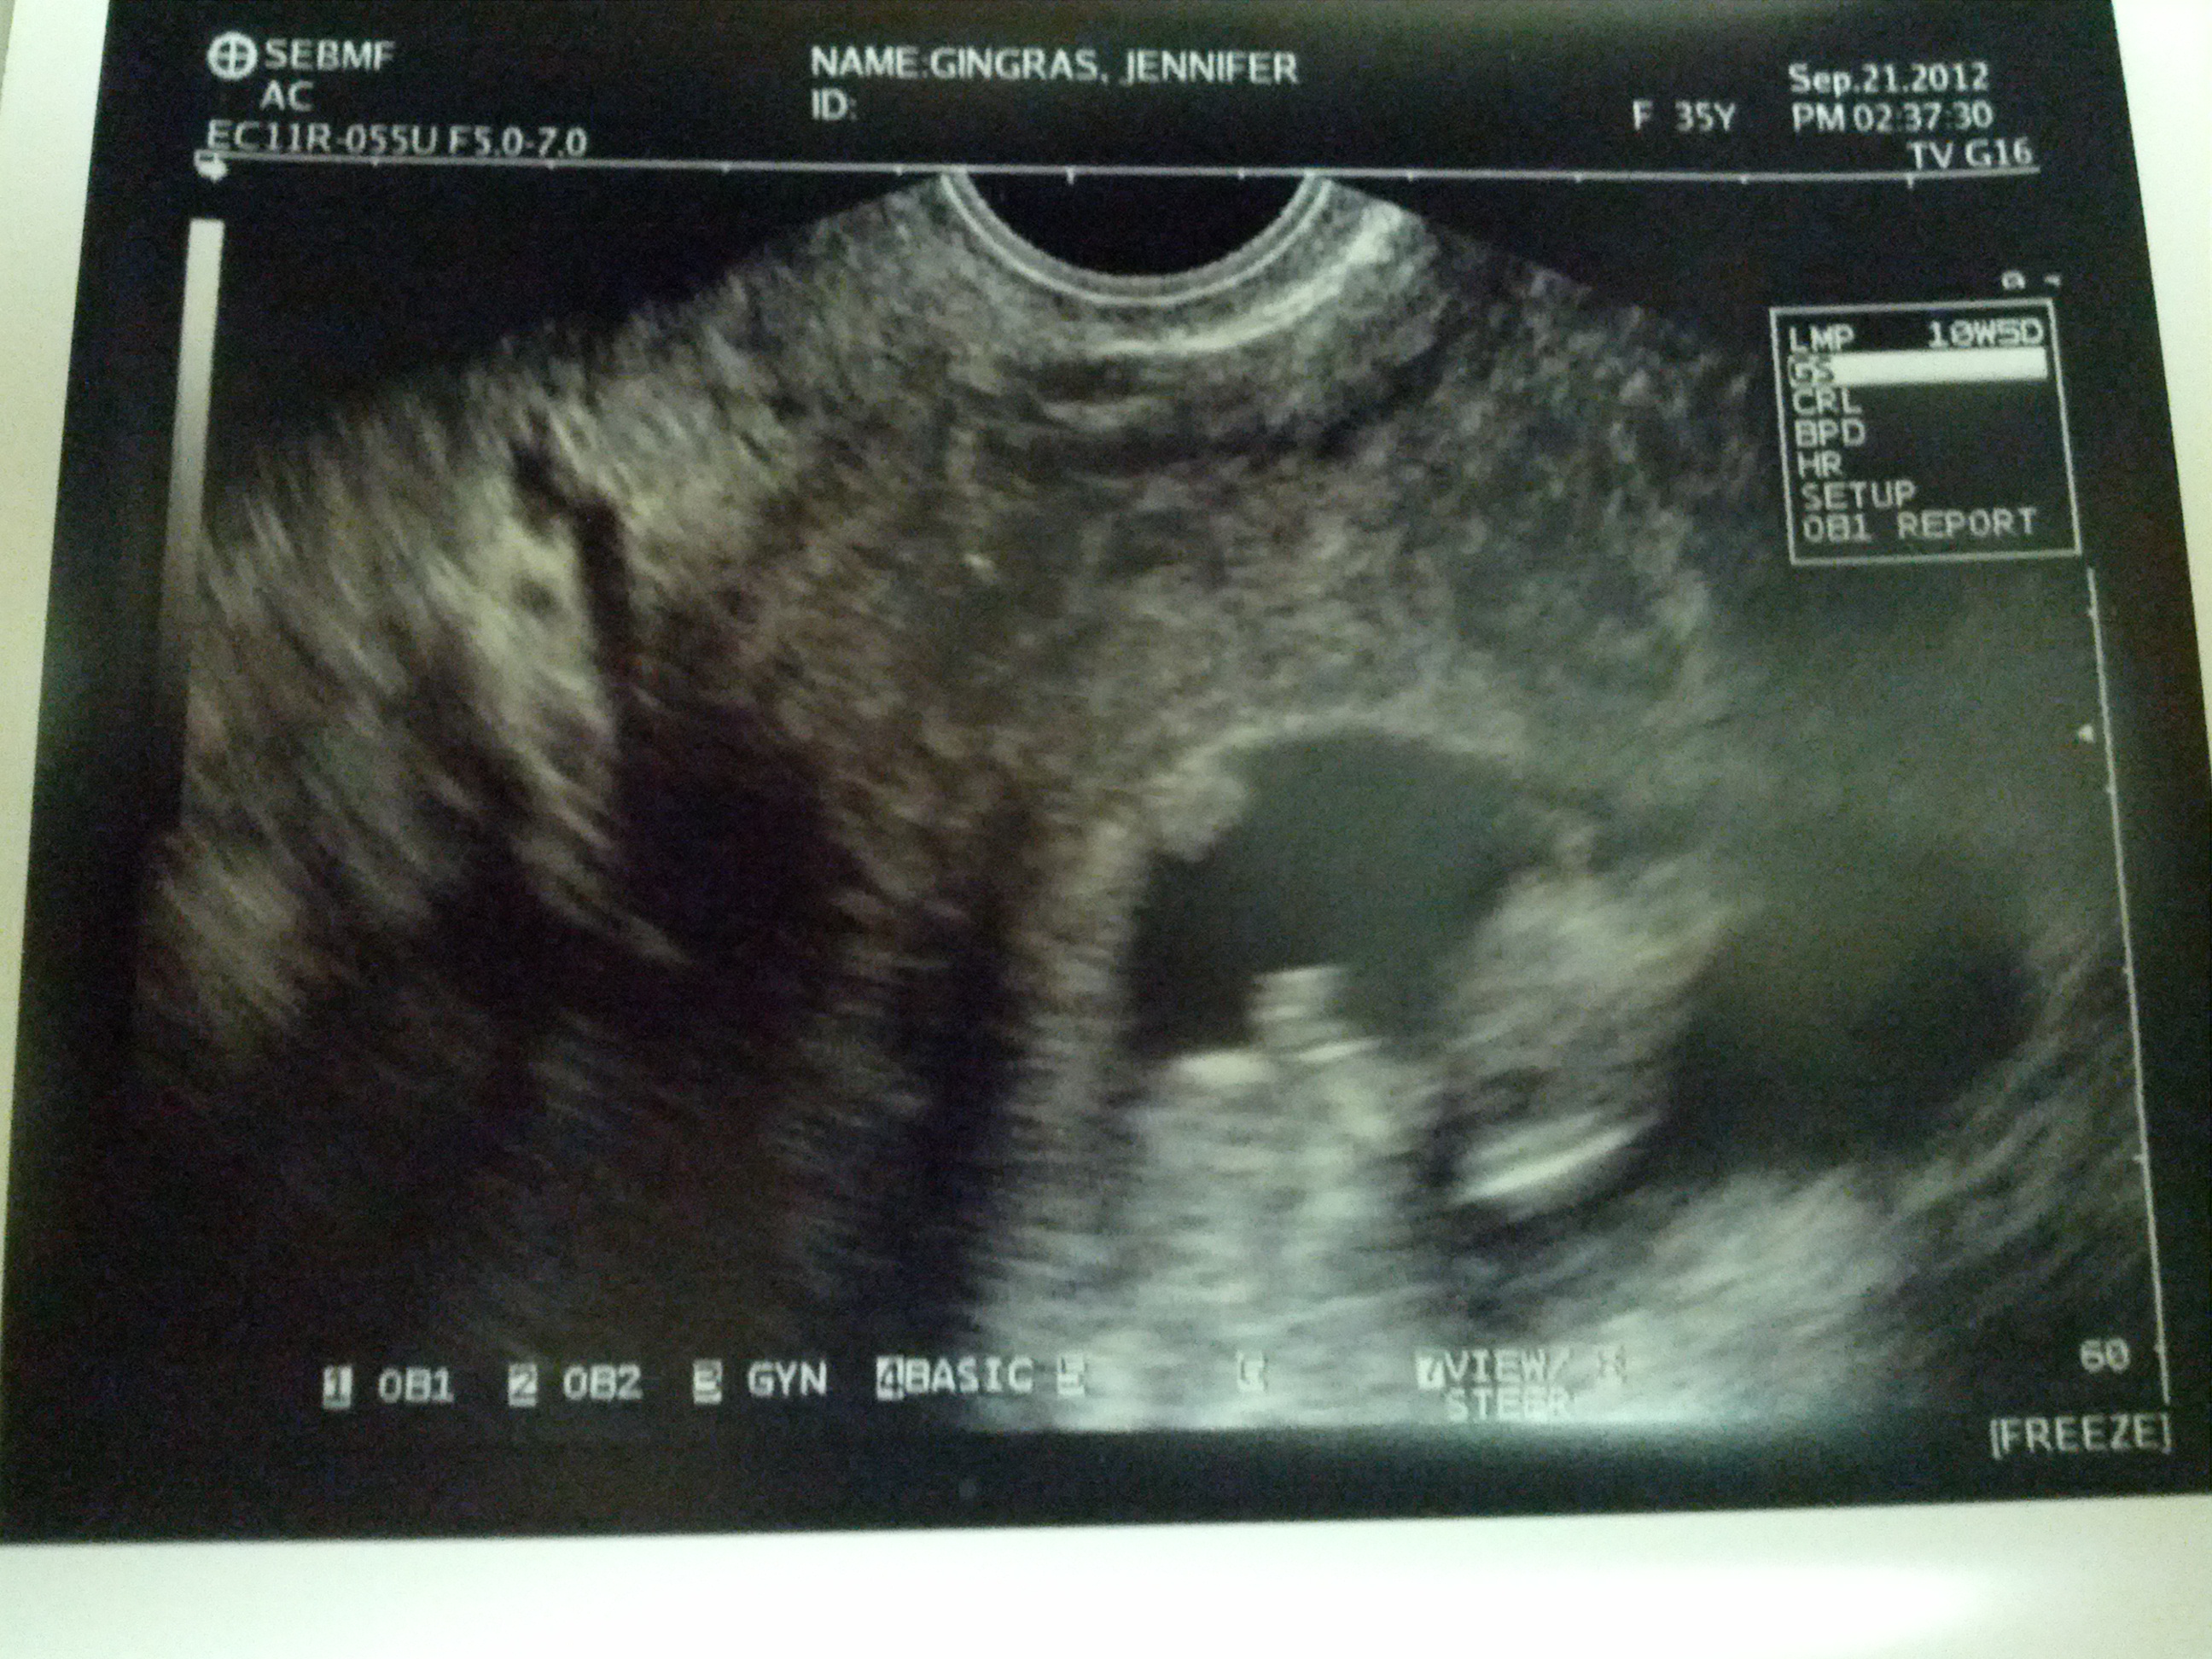

Due April 16ish, 2013:

That’s her/his head on the left, but a split second earlier, s/he was in exactly the opposite position (and that was before I started laughing). Gymnast? MMA Fighter? Trampoline enthusiast?

We can’t wait to find out. 🙂